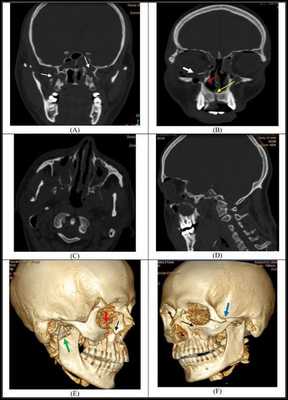

Симптоматика переломов костей средней зоны лица многообразна, поэтому для постановки точного диагноза требуется выполнение рентгенологической диагностики. Самым современным и точным методом является компьютерная томография . С её помощью челюстно-лицевой хирург имеет возможность точно определить локализацию линии разъединения костных фрагментов и тип перелома, выбрать наиболее адекватную и малотравматичную тактику лечения [11] .

1. Рентгенография нижней челюсти в обзорной (лобно - носовая укладка) и боковой (каждой половины челюсти) проекциях. При переломах мыщелкового отростка требуется проведение укладок по Шуллеру, а в некоторых случаях для уточнения направления и степени смещения малого отломка и при переломах головки височно-нижнечелюстного сустава - компьютерную томографию.